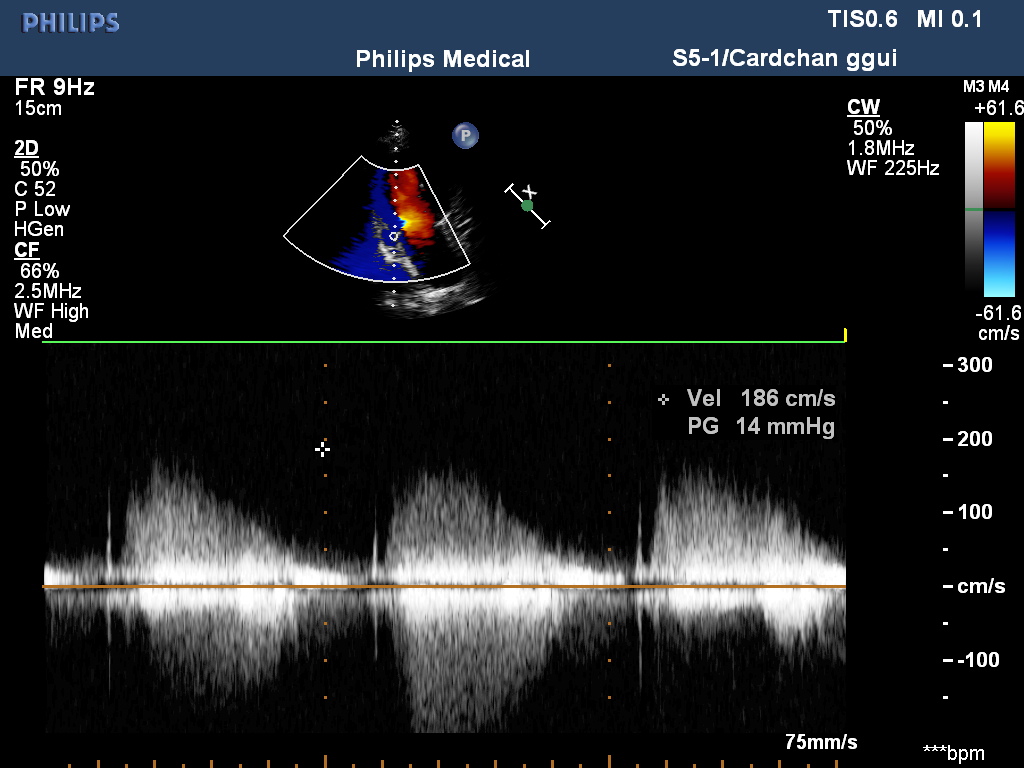

超声所见:各房室大小及大动脉根部内径正常,各瓣膜回声正常,二尖瓣,三尖瓣及主动脉瓣开启可,关闭欠佳。房室间隔连续完整,室壁厚度及运动收缩幅度正常。右冠状动脉自主动脉起始处开始迂曲扩展,较宽处内径约10mm,于二尖瓣后叶瓣环处与左室相通,开口处内径约9mm。心包腔内未见明显液性暗区。CDFI:于二尖瓣后叶瓣环处探及舒张期异常血流信号,峰值流速1.85m/s。

超声提示:1:右冠状动脉左室瘘 2:右冠状动脉迂曲扩张 3:二尖瓣、三尖瓣、主动脉瓣少量返流 4:左室舒张功能减退